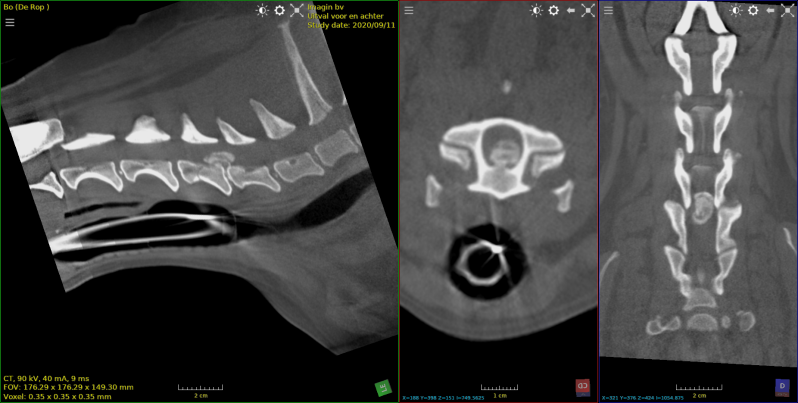

cocker met hernia  c2-c3